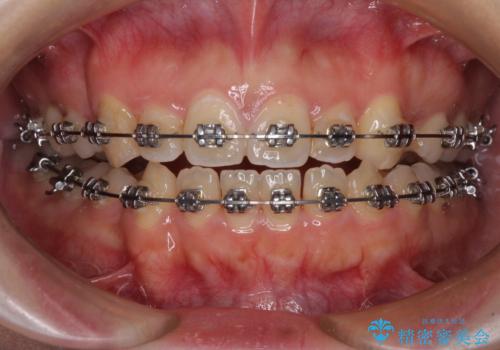

八重歯を抜歯矯正でスッキリと メタルブラケットでの矯正治療

- 八重歯と上下前歯のでこぼこを気にして来院された患者様です。

上下前歯部叢生のスペース獲得のため、上下顎左右小臼歯各1歯(計4本)と全ての親知らずを抜歯して、矯正治療を行うこととしました。

八重歯とは別に上下前歯の隙間という問題もありました。こちらは舌突出癖によるものと考えられたため、舌のトレーニングをしっかりと行っていただきました。